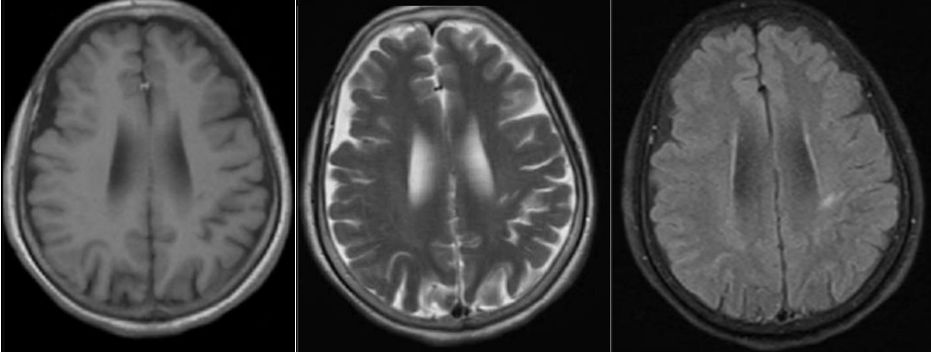

病例5

30岁女性,言语不清3年。

答案:肝豆状核变性。又称Wilson’病(WD),是一种常染色体隐性遗传的铜代谢障碍性疾病。主要是由于铜离子异常大量沉积于肝、脑、肾等组织,从而导致全身多系统多器官的损害,以神经系统症状、精神症状、眼部损害、肝脏损害等为主。神经系统最突出的症状是锥体外系症状,包括震颤、构音障碍、肌张力障碍、手足徐动症、共济失调等。构音障碍表现为声音低沉、含糊或嘶哑、缓慢或断续,严重时发不出声,是舌、唇、咽、喉和下颌肌肌张力增高所致。而肝脏的表现通常为肝功能损害、肝硬化、门脉高压症等,一般年轻患者居多。MRI表现为壳核、尾状核头和苍白球在T2WI上呈低信号,齿状核和红核亦可见T2WI为低信号。还可有不同程度的脑萎缩,如两侧壳核对称性裂隙,豆状核、尾状核、大脑皮质、脑干和小脑的萎缩。大小熊猫征为Wilson病的典型特征。